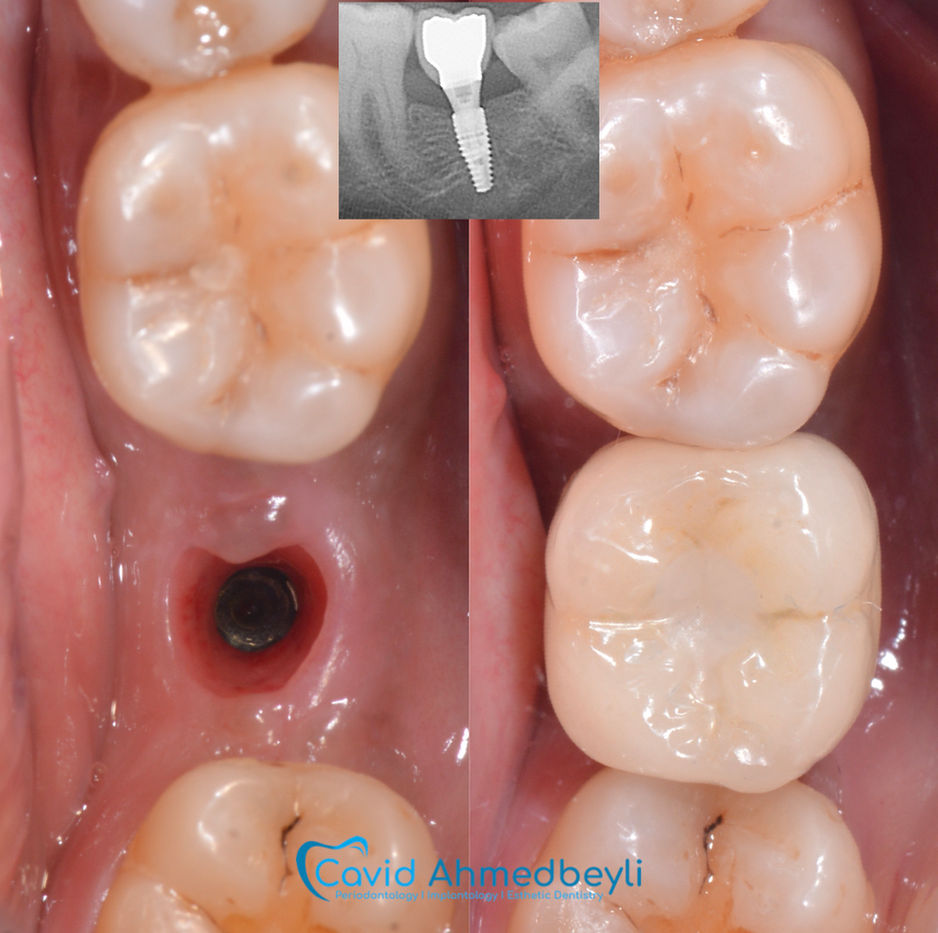

Dental implantlar - ağız boşluğunda diş əti xəstəlikləri, travma və ya digər səbəblərdən itirilmiş dişləri əvəz etmək məqsədi ilə çənə sümüyünə yerləşdirilən implantlardır. İmplantlar üçün ideal namizədlər, yaxşı ümumi və ağız boşluğu sağlamlığı olan insanlardır. İmplant planlanması sırasında ağız boşluğunda bütün müalicələr tamamlanmış, diş əti sağlam və cərrahiyyə nahiyəsində kifayət qədər çənə sümüyü həcmi və ölçüləri olmalıdır. Həkim-parodontoloq dişlər və implantlar ətrafında dəstək toxumaların xəstəliklərinin diaqnostikası, profilaktikası, qeyri-cərrahi və cərrahi müalicəsi, həmçinin ağız boşluğunda implantların yerləşdirilməsi üzrə ixtisaslaşmış həkim-stomatoloqdur.

ÖNCƏ/SONRA

Böyütmək üçün şəklin üzərinə klikləyin.